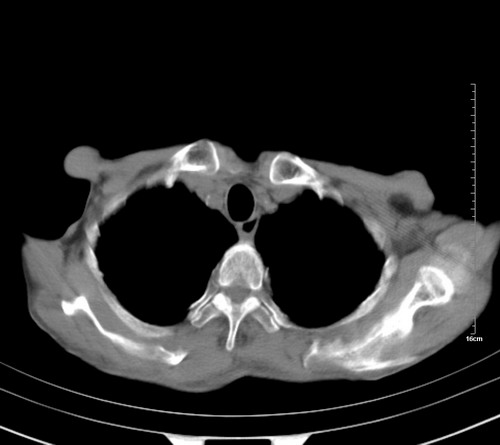

中后纵隔占位,气管、食道受压、变形、移位。恶性可能性大。

考虑:中后纵隔转移瘤可能性大,主动脉硬化。

中后纵隔转移瘤可能性大,主动脉硬化。

后中纵隔团块影,伴气管、食道受压移位,首先考虑转移瘤,肝s5段低密度灶。建议增强检查,另外其结肠是否有问题请提供,右肺部分肺叶局限含气增多,考虑局限肺气肿。

考虑:中后纵隔转移瘤可能性大,冠状动脉及主动脉硬化。